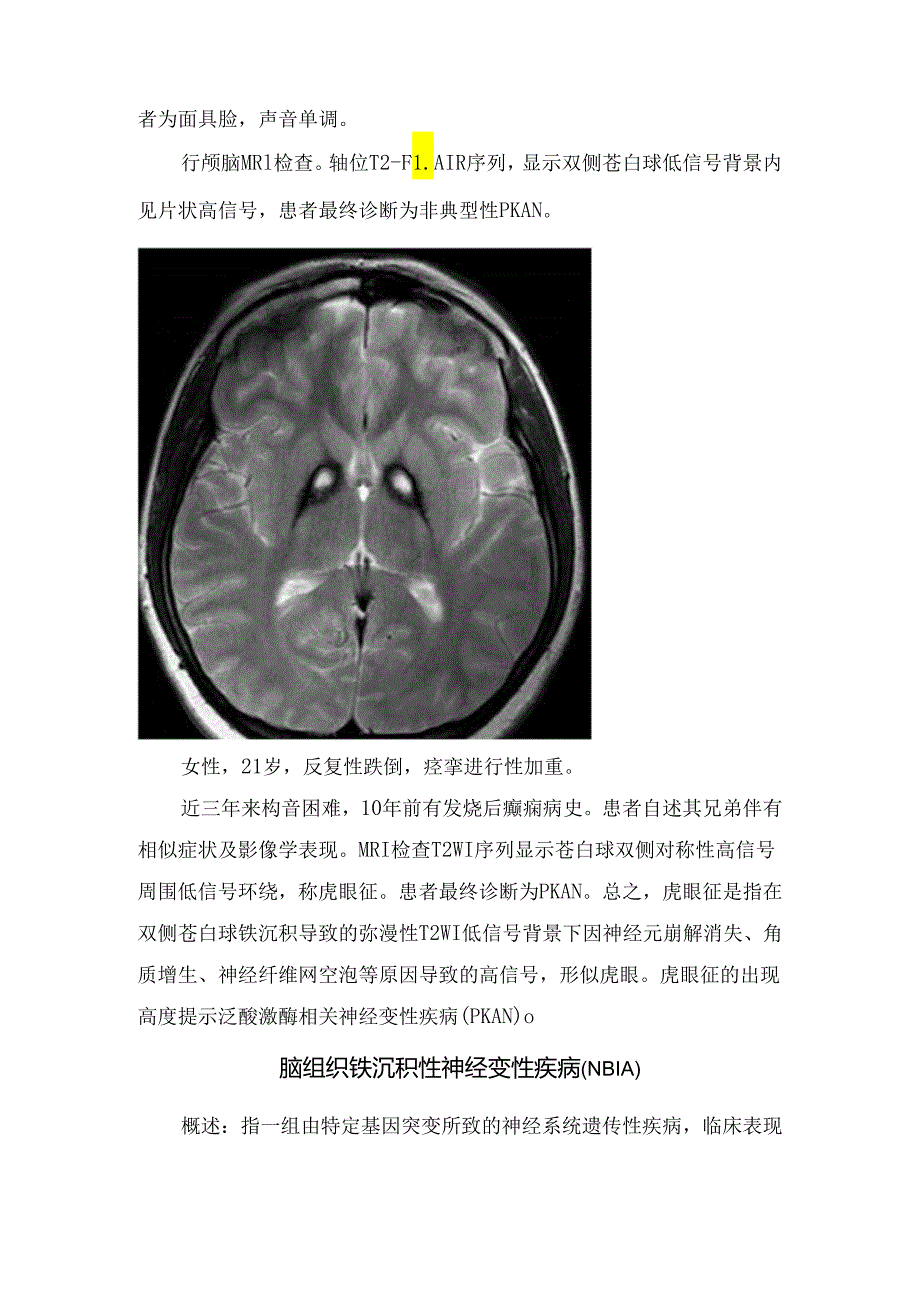

3、神经元轴索肿胀区,由于铁质的顺磁性所致;而高信号则代表病理上的疏松组织区。除了苍白球外,病变还可累及红核、齿状核,同样表现为T2WI低信号。青年患者,双手姿势性震颤10余年,查体发现患者为面具脸,声音单调。行颅脑MRl检查。轴位T2-F1.AIR序列,显示双侧苍白球低信号背景内见片状高信号,患者最终诊断为非典型性PKAN。女性,21岁,反复性跌倒,痉挛进行性加重。近三年来构音困难,10年前有发烧后癫痫病史。患者自述其兄弟伴有相似症状及影像学表现。MRI检查T2WI序列显示苍白球双侧对称性高信号周围低信号环绕,称虎眼征。患者最终诊断为PKAN。总之,虎眼征是指在双侧苍白球铁沉积导致的弥漫性T2W

4、I低信号背景下因神经元崩解消失、角质增生、神经纤维网空泡等原因导致的高信号,形似虎眼。虎眼征的出现高度提示泛酸激酶相关神经变性疾病(PKAN)o脑组织铁沉积性神经变性疾病(NBIA)概述:指一组由特定基因突变所致的神经系统遗传性疾病,临床表现主要为运动障碍、步态异常、痉挛、认知障碍等,其共同的影像学特征是脑内特定部位出现异常铁离子沉积信号。NBlA为影像学诊断,其多种疾病类型可致:1、PKAN:即上面所述HSD:约占50%。2、P1.AN:P1.A2G6相关性神经退性性疾病,占20虬3、 MPAN:线粒体膜蛋白相关性神经退行性疾病。4、 KUfOr-Rakeb病(KRD)。5、FAHNSPG3